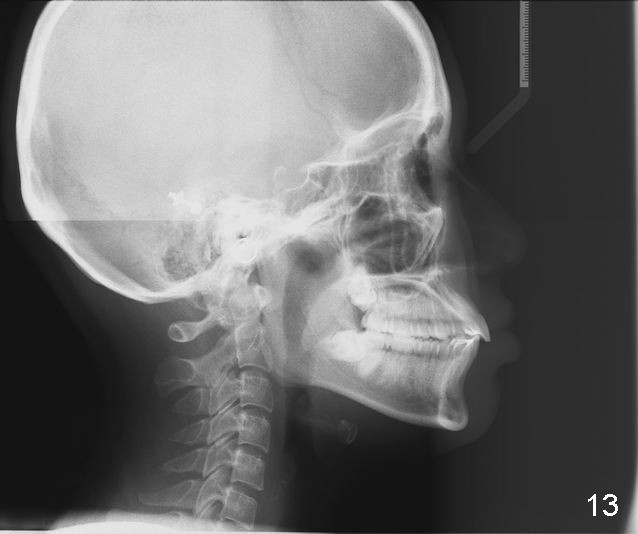

Why do the upper incisors need a lingual retainer?

Dr. Shaughnessy: Congratulation.  There is a supernumerary tooth coronal to #1.  Why do the upper incisors need a lingual retainer?

Answer: I was afraid tooth #8 would try to rotate (Fig.).  I do not like U bonded retainers as much as lower but I thought maybe in this case due to #8 initial position.  I have provided 2 removable retainers to fit over for insurance!

Excellent thinking.  According to the final photos, you must have done something to overcorrect the rotation of the two centrals.  Did you do it with purpose or by accident?  How did you do it, although Amy may not like it.  It seems to me that there is no practical way to overcorrect rotation.